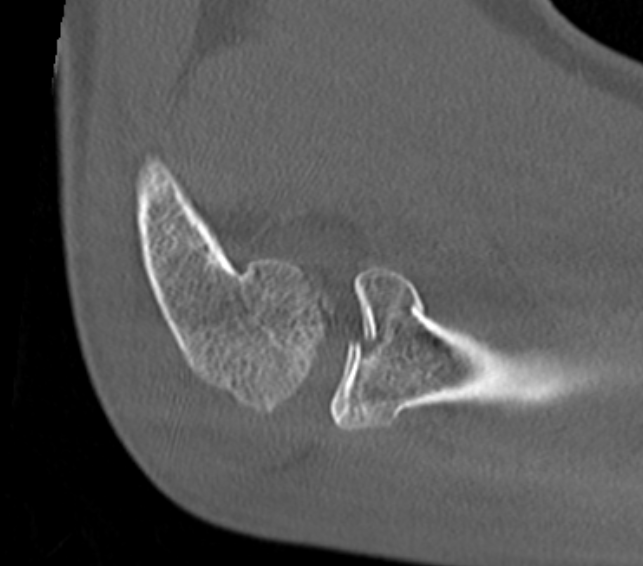

Identify safe zone for implants

- posterolateral portion of cartilage / yellow and thinner, non articulating cartilage

- 90o arc between radial styloid and Lister's tubercle